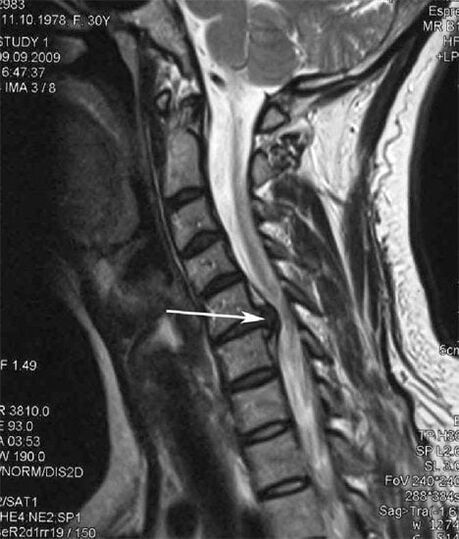

| Lepoko osteokondrosia | Bizkarrezurreko mugimendu-segmentu batean edo gehiagotan aldaketa patologikoak agertzea. Bizkarrezurreko mugikortasun urritasuna, minaren sindrome miofaszialak garatzea eta bizkarrezurreko sustraiak apurtzea | Trápaga eskualdean mina, parestesia eta asaldura motorrak, buruaren atzealdera eta goiko gorputz-adarrera hedatzen direnak. MRI eta erradiografietan bizkarrezurreko aldaketa ezaugarriak hautematea (osteofitoak, ornoen arteko distantzia gutxitzea, orno arteko artikulazioetan kaltearen seinaleak) |

Hasierako faseetan, osteokondrosia detektatzen da MRI bidez. Geroago, patologia erradiografia erabiliz diagnostikatu daiteke. Trápaga bizkarrezurraren erradiografietan, ornoen arteko distantziaren murrizketa, giltzaduretako alderdietako aldaketa patologikoak eta osteofitosia nabaritzen dira.